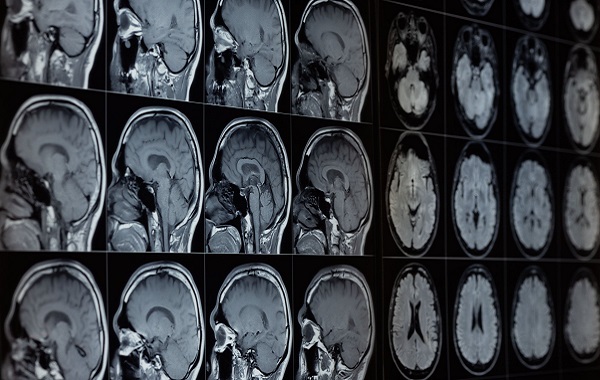

The brains of people with Alzheimer’s are different in many ways from others. In particular, they contain high levels of misfolded amyloid beta and tau, two proteins that normally have important functions. But these aren’t the only changes seen in Alzheimer’s. And it was while investigating these other changes that the Harvard researchers made their discovery.

With the help of existing projects that collected postmortem tissue samples, they compared levels of around 30 metals in the brains of people who died along varying stages of cognitive health. The only major difference they found was with lithium. People with cognitively healthy brains had relatively high levels of lithium, whereas those with Alzheimer’s had much lower levels. Importantly, this loss of lithium was apparent even in people who only experienced mild memory problems before dying.

The researchers also studied healthy mice and genetically modified mice that develop a version of Alzheimer’s disease. When they depleted lithium from these mice, it appeared to accelerate the buildup of unhealthy amyloid beta and tau in the brain, along with memory decline. They also found evidence that this loss is caused by amyloid beta plaques binding to the brain’s lithium and that this loss of lithium seems to negatively affect all of the brain’s major cell types.